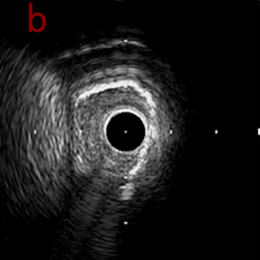

PreのIVUSではaの部位のみlipid plaqueを認め削ることでdistal embolismのリスクがあり、そのほかは270度の偏心性石灰化であるがwire biasは良好。

Pre